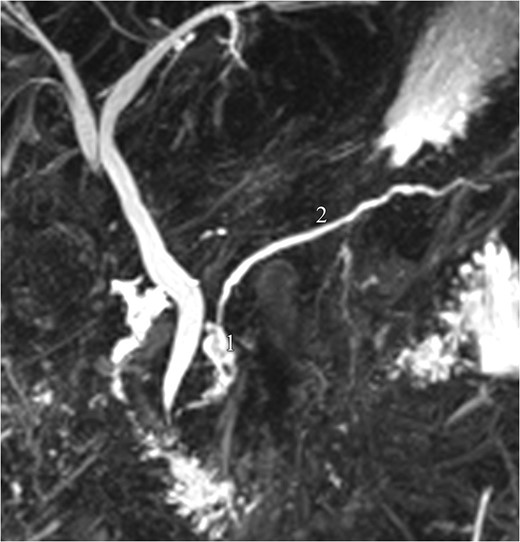

Magnetic resonance pancreatography (1 month after trauma): leak of pancreatic fluid (1), arising from the cephalic part of the main pancreatic duct (2), consistent with a ductal laceration.